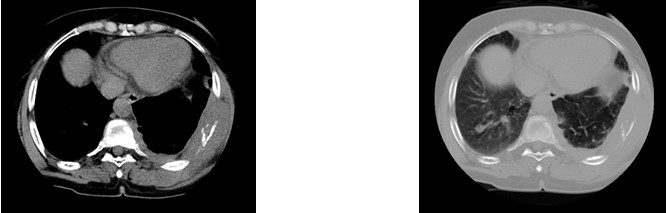

Volver a los detalles del artículo Linfoma difuso de células B grandes